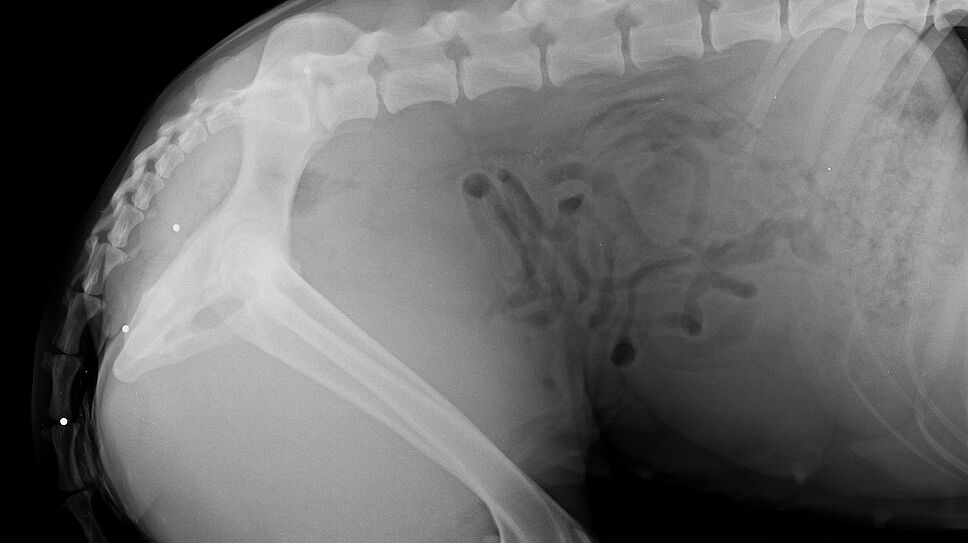

La série noire continue, dans une indifférence générale apparente… Après le pauvre Vegas touché par 50 à 70 plombs (19/12/2020) et Ounka, retrouvée morte elle aussi criblée de plombs (20/12/2020), c’est Aimer, une chienne de 2 ans et demi qui a été victime d’une arme de chasse. Le beauceron croisé malinois a reçu 8 impacts de plombs : au niveau des pattes arrière, de la queue, de l’arrière-train, du ventre et d’une oreille (30/12/2020).

La chienne gardera plusieurs plombs dans le corps que le vétérinaire ne pouvait pas retirer./DR